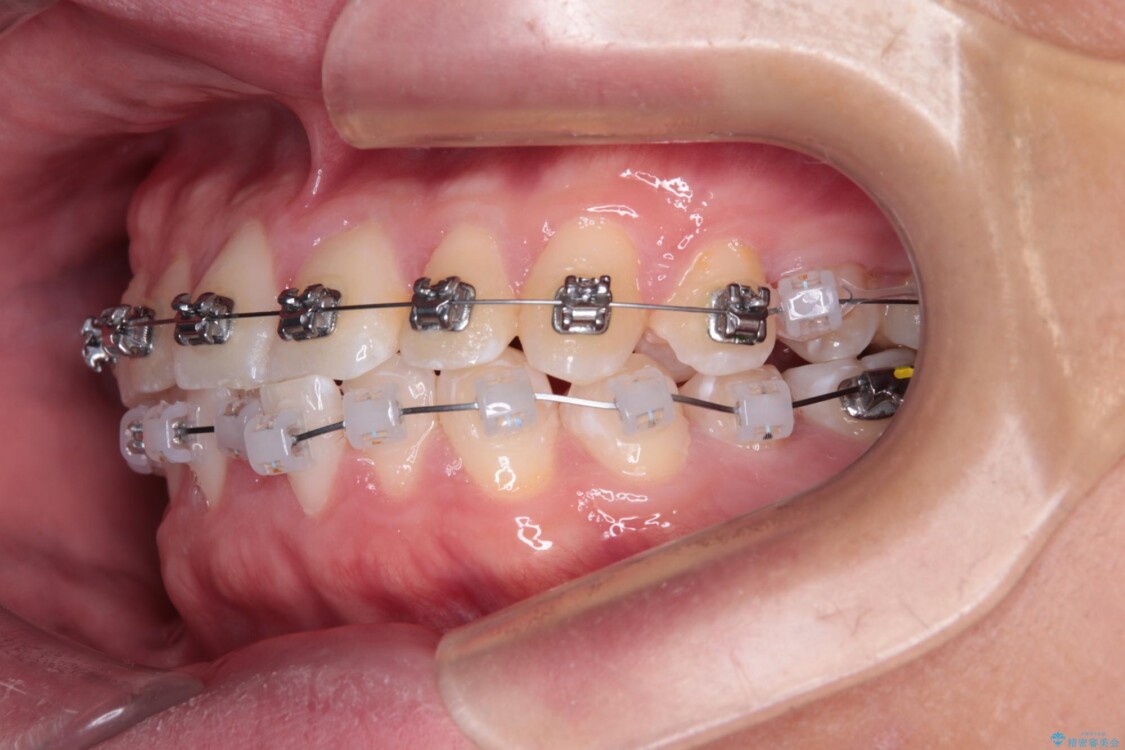

治療途中

• 前歯のガタガタ・奥歯のかみ合わせ(シザーズバイト)を改善|1年半で完了したメタルブラケット矯正 治療途中画像